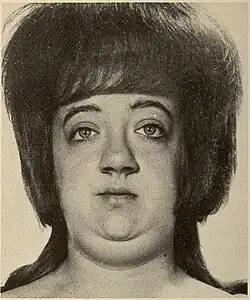

| Woman with pycnodysostosis | |

The disease was first described by Maroteaux and Lamy in 1962[4][5] at which time it was defined by the following characteristics: dwarfism; osteopetrosis; partial agenesis of the terminal digits of the hands and feet; cranial anomalies, such as persistence of fontanelles and failure of closure of cranial sutures; frontal and occipital bossing; and hypoplasia of the angle of the mandible.[6] The defective gene responsible for the disease was discovered in 1996.[7] The French painter Henri de Toulouse-Lautrec (1864–1901) is believed to have had the disease.[8]

Pycnodysostosis causes the bones to be abnormally dense; the last bones of the fingers (the distal phalanges) to be unusually short; and delays the normal closure of the connections (sutures) of the skull bones in infancy, so that the "soft spot" (fontanelle) on top of the head remains widely open.[9] Because of the bone denseness, those with the syndrome suffer from fractures.[7]

Other abnormalities involve the head and face, teeth, collar bones, skin, and nails. The front and back of the head are prominent. Within the open sutures of the skull, there may be many small bones (called wormian bones). The midface is less full than usual. The nose is prominent. The jaw can be small. The palate is narrow and grooved. There will be delay in fall of milk teeth. The permanent teeth can also be slow to appear. The permanent teeth are commonly irregular and teeth may be missing (hypodontia). The collar bones are often underdeveloped and malformed. The nails are flat, grooved, and dysplastic. High bone density, acro-osteolysis and obtuse mandibular angle are the characteristic radiological findings of this disorder.[10]

Pycnodysostosis is one of those disorders which has a typical facial gestalt[15] and can be clinically identified in the majority of cases. Skeletal surveys can also aid in clinical diagnosis and characteristic features include high bone density, acro-osteolysis and obtuse mandibular angle. Molecular testing will be the final resort to confirm the diagnosis. Due to the limited number of exons of the CTSK gene that causes pycnodysostosis, a cheaper genetic testing called Sanger sequencing can be employed to confirm the diagnosis.